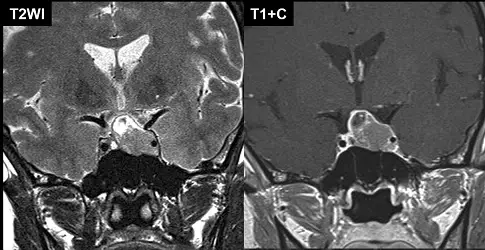

53歲女性,一個月來有頭痛現象,根據所附二張MRI影像,下列何者為最可能的診斷?

suprasellar與sellar區塊的常見病灶,以pituitary macroadenoma、meningioma、aneurysm為主體,其中pituitary macroadenoma為成人最常見之suprasellar腫塊 (radiopaedia.org)。本題重點在於透過MRI影像特徵加以鑑別節段性病灶。

左圖(T2WI coronal)見鞍窩區塊狀病變,signal較周遭結構等至輕度高,鞍底明顯擴大且骨質呈漸進式改建;病灶向上延伸至鞍上,與周圍腦組織界限清晰,無大量周圍水腫。右圖(T1+C coronal)顯示該病灶呈均質強化,無中央壞死或囊化,也未見典型的硬膜尾(dural tail)或骨質破壞,整體呈現“雪人”或figure-of-eight形態。

- 選項A 內頸動脈動脈瘤

專利動脈瘤於T2WI常見flow void(低訊號),或呈非均質血流回聲;增強序列可見血池填充,但不呈固態均質強化,且T2一般為低訊號 ([radiopaedia.org](https://radiopaedia.org/articles/saccular-cerebral